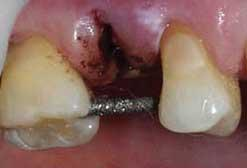

This patient had a significant social event one week after we observed the condition. An upper 2nd bicuspid had split and was badly infected. Antibiotics to help get her through the event was not an option. The best solution was immediate removal of the tooth with proper debridement of the socket. Removal of the tooth, however, created a different problem because a space would then be obvious in the smile line and the upcoming social event involved important close-up photos. The need for immediate cosmetic replacement of the tooth pointed to either preparing adjacent teeth for a three-unit bridge or an adhesively bonded cosmetic pontic. Since the abutment teeth were sound with no indication for crowns, we suggested a more conservative, less costly immediate option, keeping open the possibility of replacement in the future with an implant and crown.

As the case photos show, the tooth was removed, the socket cleaned, and bleeding controlled. After the tooth was extracted, the crown portion was sectioned and reshaped to serve as the framework for a composite pontic. Preparation of the adjacent abutment teeth was limited to proximal slots to fit a metal reinforcment rod for increased strength. A diamond bur was sectioned to use as the supportive rod. A fourth-generation bonding agent (Optibond FL) was chosen for adhesion. A highly polishable nanofilled composite (Premise) in a single shade A2 was used to rebuild the pontic into the space around the supporting rod. A Demetron Demi portable LED was used to cure the materials. Polishing discs and points were used to create a high-luster finish. The introduction of nano particles to hybrid composites combines the best qualities of each: the strength of hybrid composites and the polishability of microfills. I have observed these products at recall appointments and noticed a self-polishing effect with gloss retained and stain retention minimized.